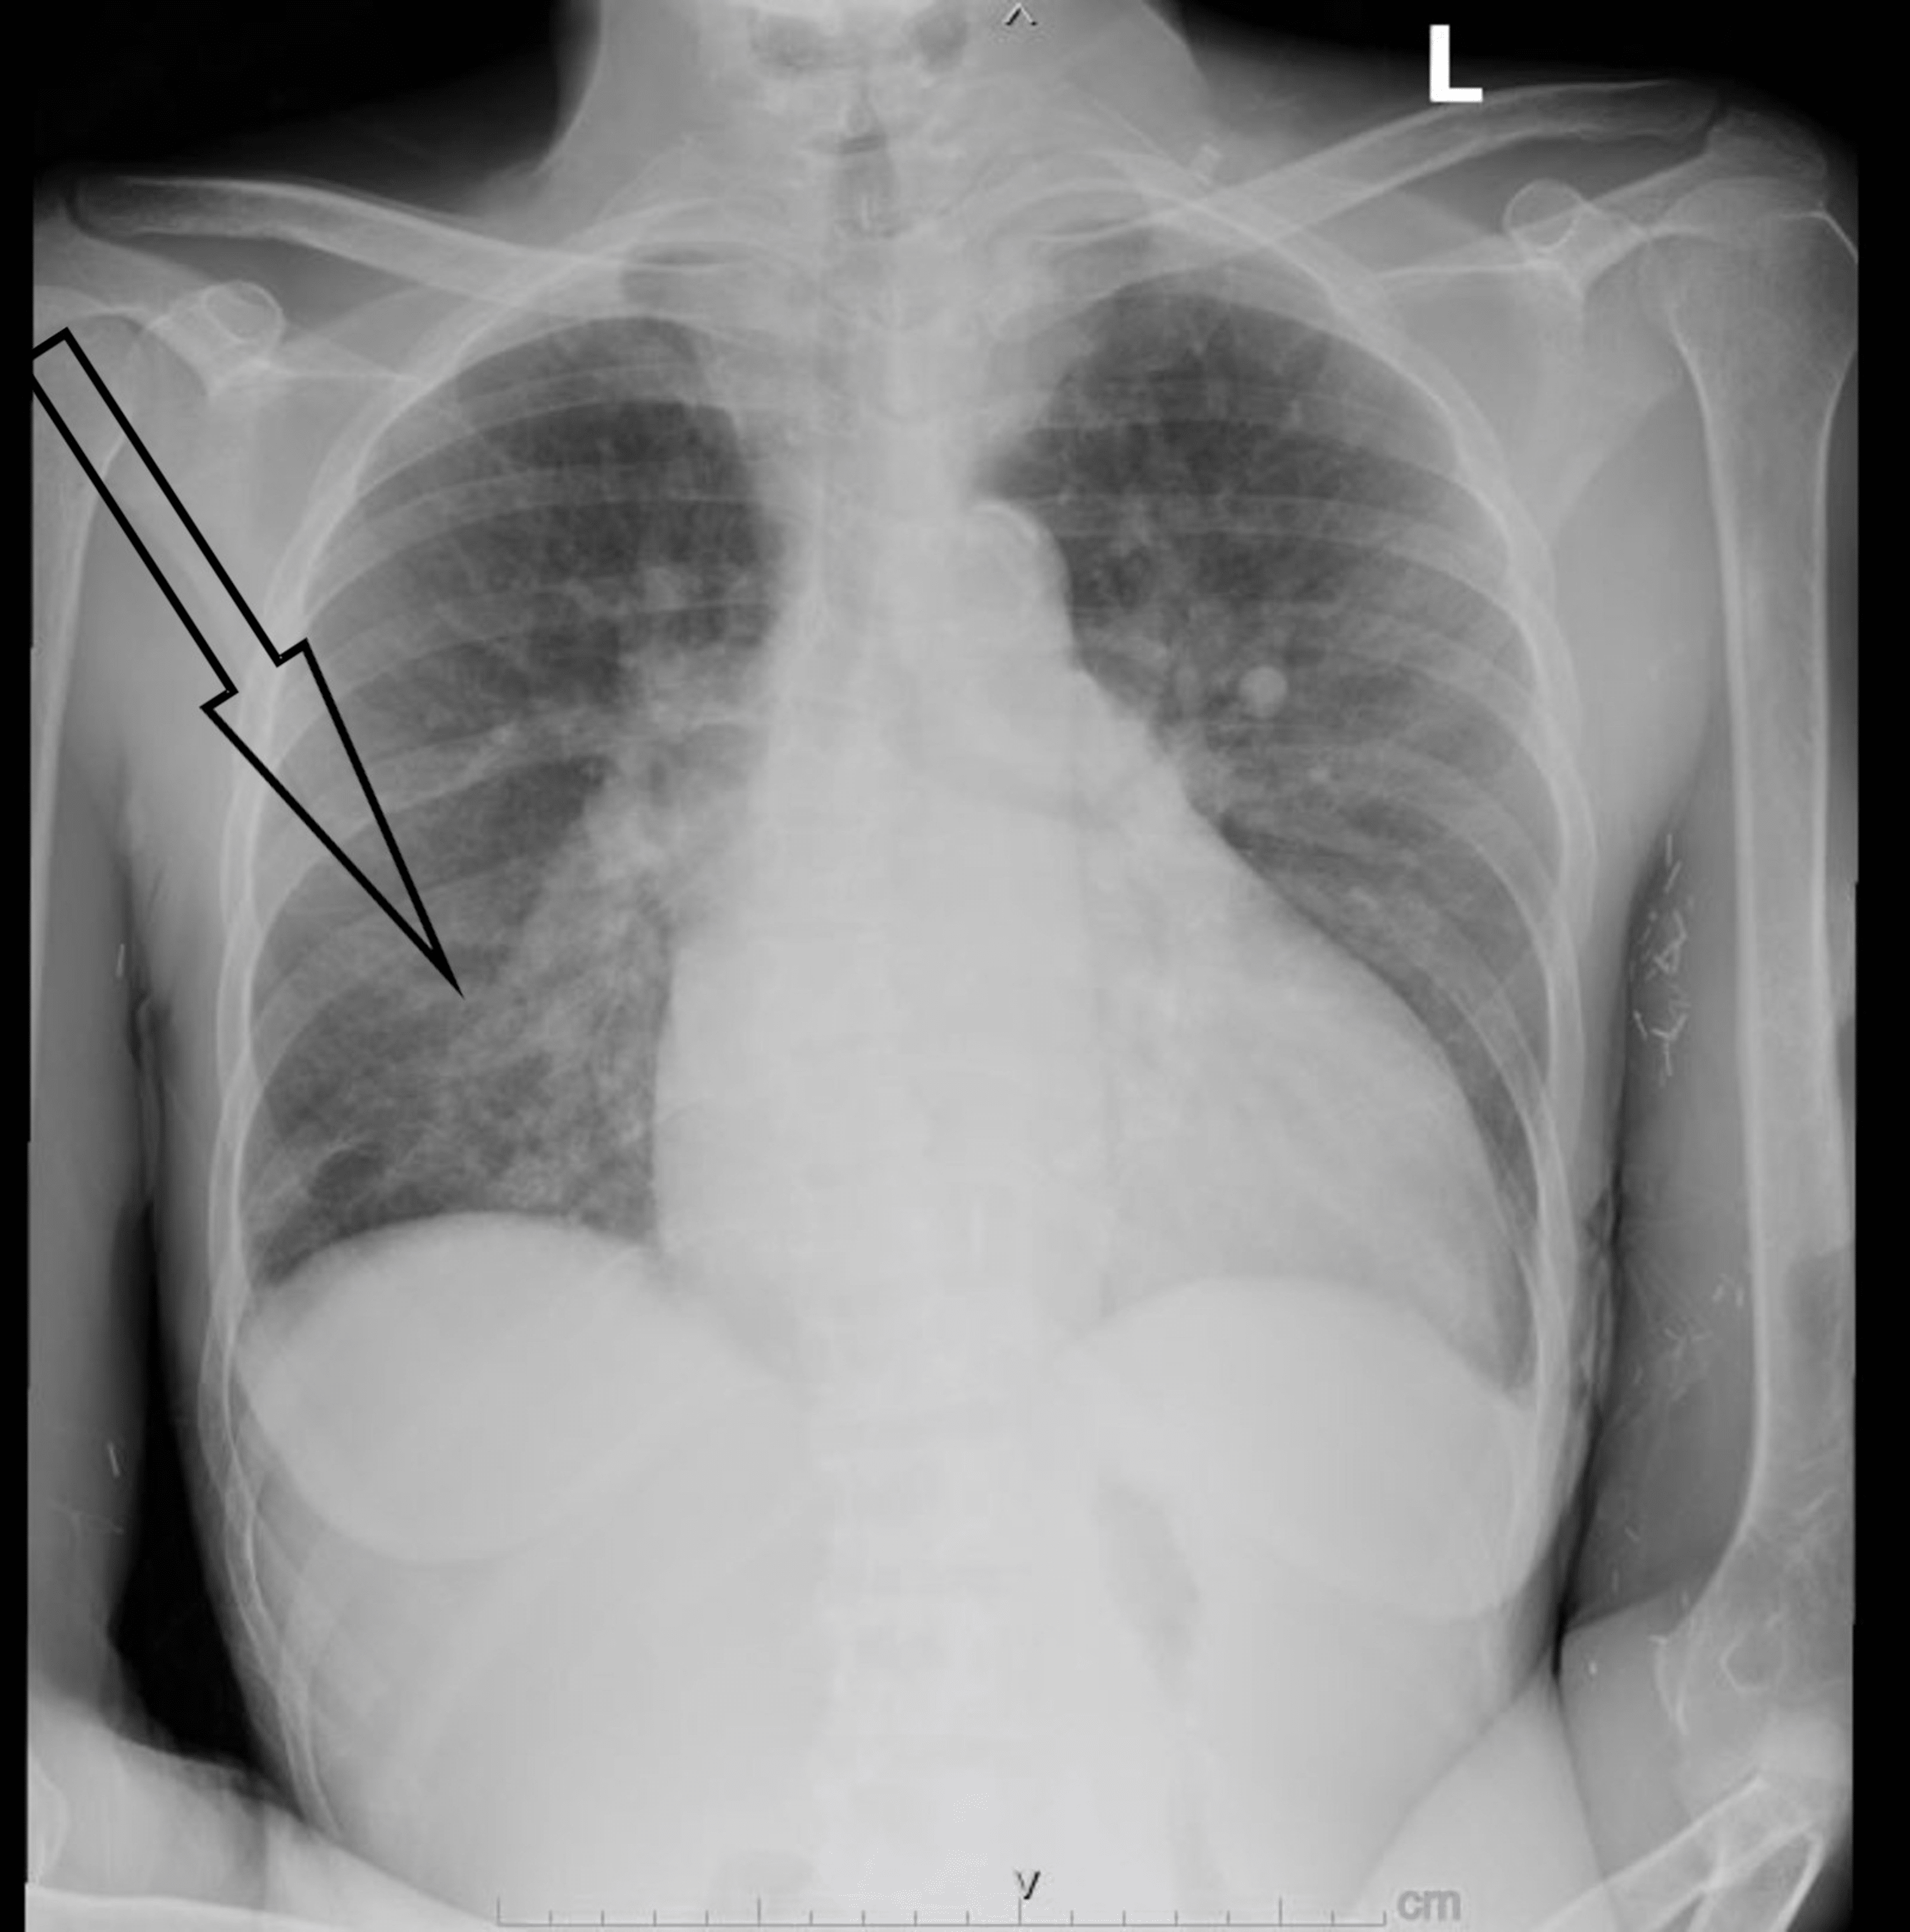

Staphylococcus Aureus Endocarditis Complicated by Aortic Root Abscess Staph Infection Heart Valve Infective endocarditis is an infection caused by bacteria that enter the bloodstream and settle in the heart lining, a heart valve or a blood vessel. Treatment includes several weeks of. Review the appropriate evaluation skills required to assess suspected cases of infective endocarditis. It's a serious condition that needs to be treated right away. Endocarditis is a serious infection of. Staph Infection Heart Valve.

Echocardiographic, Histopathologic, and Surgical Findings in Staph Infection Heart Valve It's a serious condition that needs to be treated right away. Infective endocarditis is a rare bacterial infection affecting your heart valves. Bacterial endocarditis is an infection of the heart’s inner lining or heart valves. Infective endocarditis is an infection caused by bacteria that enter the bloodstream and settle in the heart lining, a heart valve or a blood vessel.. Staph Infection Heart Valve.

Echocardiographic, Histopathologic, and Surgical Findings in Staph Infection Heart Valve Staph bacteria can also damage the heart valves and lead to heart failure. Summarize the etiology of infective endocarditis. When bacteria release toxins into your body, a. Endocarditis, most often from a bacterial infection, inflames the lining of your heart valves and chambers. Endocarditis is a serious infection of the heart's inner lining, often caused by bacteria. It can damage. Staph Infection Heart Valve.

Echocardiographic, Histopathologic, and Surgical Findings in Staph Infection Heart Valve Summarize the etiology of infective endocarditis. Bacterial endocarditis is an infection of the heart’s inner lining or heart valves. Review the appropriate evaluation skills required to assess suspected cases of infective endocarditis. Staph bacteria can also damage the heart valves and lead to heart failure. Infective endocarditis is a rare bacterial infection affecting your heart valves. Timely treatment with antibiotics. Staph Infection Heart Valve.